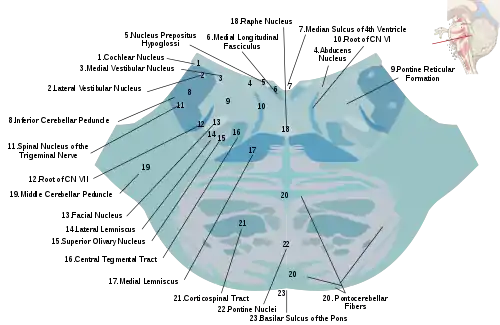

Corticobulbar tract

Fibres from the ventral motor cortex travel with the corticospinal tract through the internal capsule, but terminate in a number of locations in the midbrain (cortico-mesencephalic tract), pons (Corticopontine tract), and medulla oblongata (cortico-bulbar tract).[6] The upper motor neurons of the corticobulbar tract synapse with interneurons or directly with the lower motor neurons located in the motor cranial nerve nuclei, namely oculomotor, trochlear, motor nucleus of the trigeminal nerve, abducens, facial nerve and accessory and in the nucleus ambiguus to the hypoglossal, vagus and accessory nerves.[6] These nuclei are supplied by nerves from both sides of the brain, with the exception of the parts of the facial nerve that control muscles of the lower face. These muscles are only innervated by nerves from the contralateral (opposite) side of the cortex.[6]

Corticospinal tract

Nerve fibres in the corticospinal tract originate from pyramidal cells in layer V of the cerebral cortex. Fibres arise from the primary motor cortex (about 30%), supplementary motor area and the premotor cortex (together also about 30%), and the somatosensory cortex, parietal lobe, and cingulate gyrus supplies the rest.[2] The cells have their bodies in the cerebral cortex, and the axons form the bulk of the pyramidal tracts.[4] The nerve axons travel from the cortex through the posterior limb of internal capsule, through the cerebral peduncle and into the brainstem and anterior medulla oblongata. Here they form two prominences called the medulla oblongatary pyramids. Below the prominences, the majority of axons cross over to the opposite side from which they originated, known as decussation. The axons that cross over move to the outer part of the medulla oblongata and form the lateral corticospinal tract, whereas the fibres that remain form the anterior corticospinal tract.[2] About 80% of axons cross over and form the lateral corticospinal tract; 10% do not cross over and join the tract, and 10% of fibres travel in the anterior corticospinal tract.